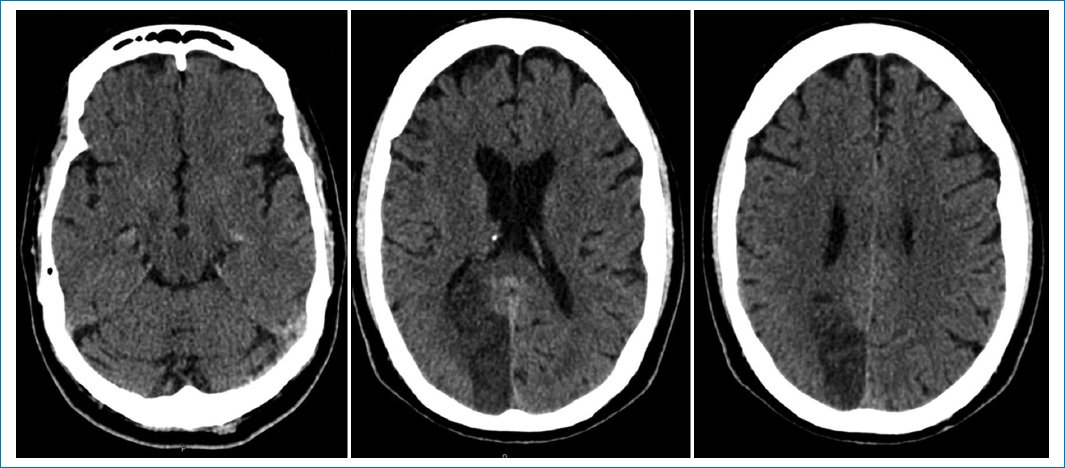

The electrocardiogram was relevant for persistent ST elevation on leads V2 and V3, T-wave inversion of leads DI, aVL, V2-V6, and Q-wave in leads DI, aVL, V1-V3, suggestive of an evolved anterior ST-elevation myocardial infarction (STEMI) (Fig. 1). The results of blood tests revealed high levels of troponin and brain-type natriuretic peptide (Table 1). The computed tomography (CT) scan of the head showed an ischemic infarct in the posterior cerebral artery territory (Fig. 2). The transthoracic echocardiogram (TTE) revealed dyskinesia of the apical septal, mid-inferoseptal, apical anterior, and mid-anterior walls; hypokinesia in the basal inferoseptal, apical lateral, mid-anterolateral, and basal anterior walls; and akinesia in the apical inferior, anteroseptal, and apical lateral walls of the left ventricle. The patient had a left ventricular ejection fraction (LVEF) of 36%, no right ventricular systolic dysfunction, and no valvulopathies (Fig. 3).

Figure 2. Non-contrast computed tomography showing a posterior cerebral artery infarct.